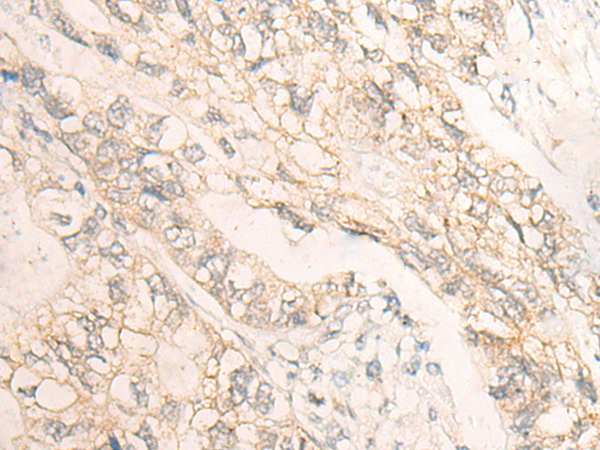

IHC positive control: |

Human gastric cancer; |

IHC Recommend dilution: |

20-100 |